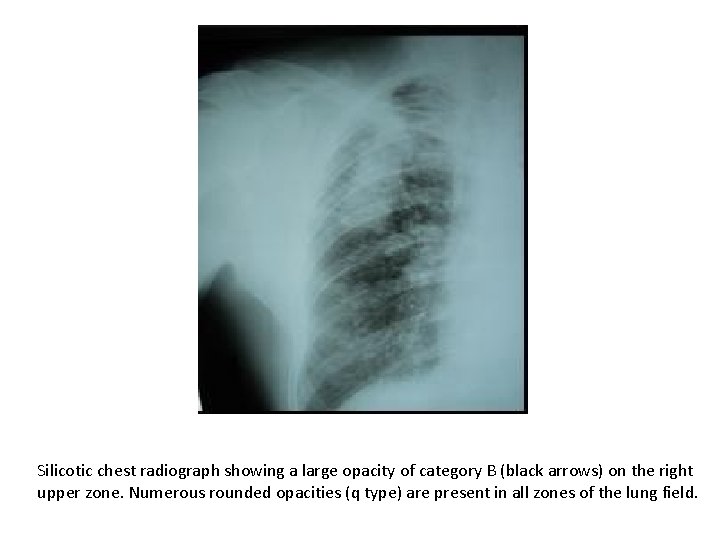

Silicotic chest radiograph showing a large opacity of category B (black arrows) on the right upper zone. Numerous rounded opacities (q type) are present in all zones of the lung field.